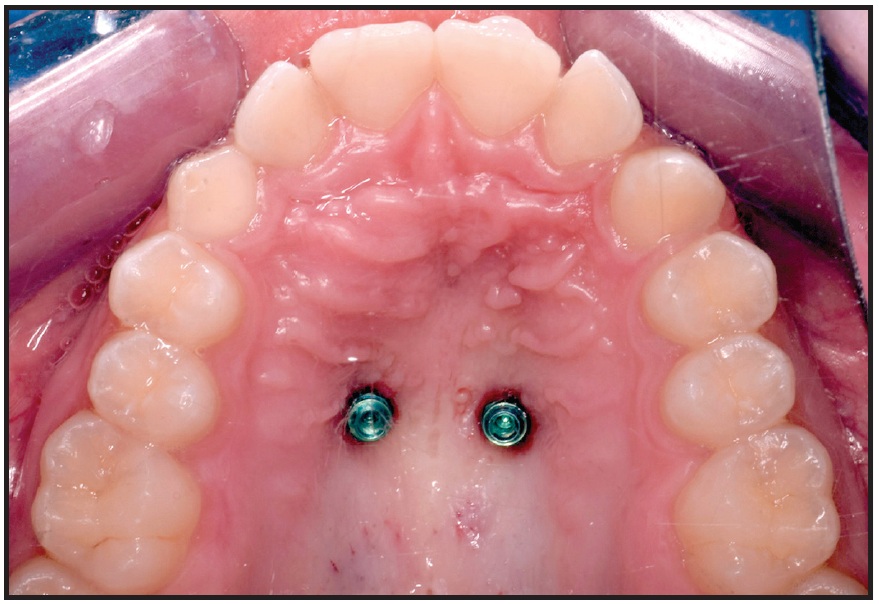

Fig. 9 Two parallel miniscrews after insertion in anterior palate.

After impression transfer copings were placed over the miniscrew heads, a precision impression was taken with vinyl polysiloxane, and the miniscrew positions were replicated with two analogs (Fig. 10). A hybrid Hyrax‡‡ expander was fabricated with an anterior arm on the right side and an attached eyelet that would serve as an occlusal guide for traction of the impacted canine (Fig. 11). The arm was designed to generate a force vector capable of moving the canine crown distally and occlusally, thus facilitating guided eruption.